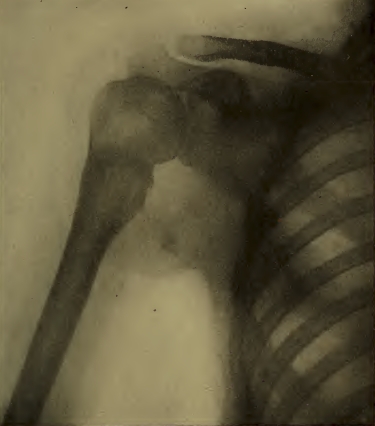

PLANCHE V. — Radiographie d'une épaule. Les parties des côtes qui sont les plus rapprochées de la plaque donnent des ombres nettes et étroites; les parties plus éloignées donnent des ombres moins nettes et élargies.

La planche V nous montre la radiographie d'un thorax, sur laquelle on reconnaît les déformations inévitables de la projection. Les côtes apparaissent très élargies dans leurs portions éloignées de la plaque, par rapport aux portions rapprochées de la plaque.